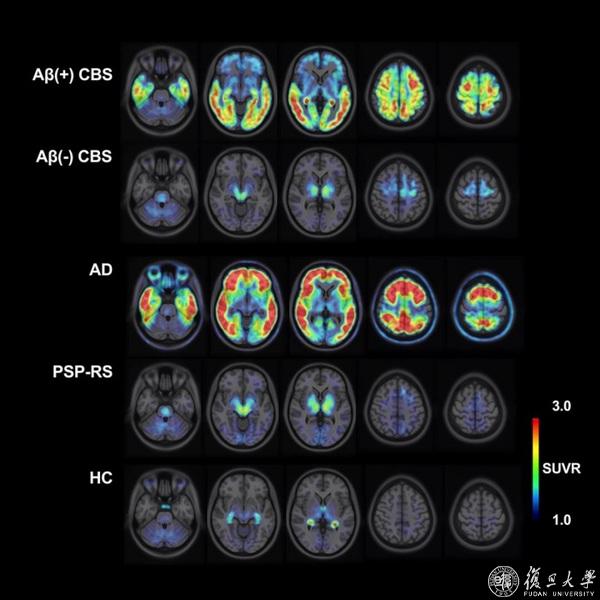

王坚、管一晖、左传涛团队合作提出新型tau蛋白PET显像示踪剂18F-Florzolotau在体可视化显像皮质基底节综合征(CBS)患者脑中tau蛋白的病理分布特点

近日,国家神经疾病医学中心、复旦大学附属华山医院神经内科王坚教授和核医学科/PET中心管一晖、左传涛教授团队基于患者脑影像研究队列数据,在国际上首次报道了新型tau蛋白PET显像示踪剂18F-Florzolotau在体可视化显像皮质基底节综合征(CBS)患者脑中tau蛋白的病理分布特点,并提出18F-Florzolotau是极具潜力可用于CBS鉴别诊断和严重度评估的客观影像学标志物。该研究以18F-Florzolotau positron emission tomography imaging of tau pathology in the living brains of patients with corticobasal syndrome为题在全球神经病学运动障碍领域顶尖期刊Movement Disorders(《运动障碍》)在线发表,并被作为二月份顶尖文章(Top Articles)进行推荐。